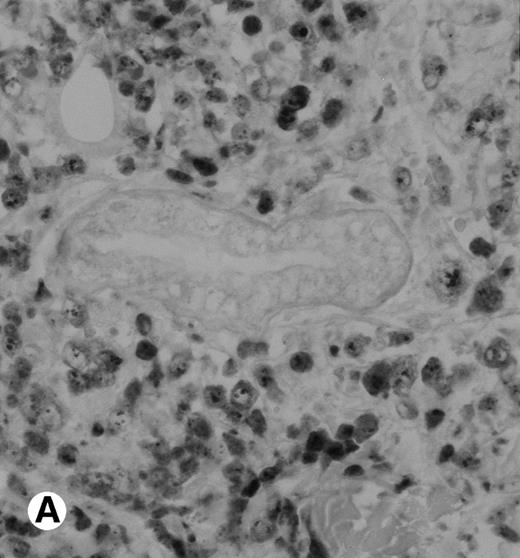

The polyclonal anti-p80 provided a staining of some large cells of 1 of the 11 LyP (case no. 4). A cytoplasmic staining of lymphomatous cells was also seen in 4 of the 15 CD30+ primary CTCL (cases no. 5, 6, 8, and 9) and in 3 of the 11 CD30+ secondary cutaneous lymphomas (cases no. 1, 2, and 3). Keratinocytes or dendritic cells of the dermis were sometimes stained by anti-p80. All p80+ cases were previously shown to contain NPM-ALK transcripts by nested RT-PCR. However, not all cases with NPM-ALK chimeric transcripts were stained by p80+. No p80+ cells were detected in MF and BID sections. The staining with the monoclonal ALK1 antibody was cytoplasmic and nucleolar and restricted to tumoral cells of CD30+lymphomas. Only 1 case of CD30+ primary CTCL was ALK1+ (case no. 8; Fig 3). This case was 1 of the 2 cases with a positive standard RT-PCR amplification, whereas the other 1 was found to be negative for both p80 and ALK1 immunostaining (case no. 10). The 3 cases of CD30+ secondary CTCL with NPM-ALK transcripts were stained for ALK1 (cases no. 1, 2, and 3; Fig 3). No ALK1-immunoreactive cell was found in LyP sections and no labeling of the epidermis was observed. None of the cases with a negative NPM-ALK detection by RT-PCR and none of the MF and BID was found to be stained for ALK1.

Immunohistochemical detection of chimeric NPM-ALK protein (×400). A case of CD30+ primary CLCL (case no. 8; A) and a case of CD30+ secondary CLCL (case no. 1; B) both with a positive NPM-ALK amplification by both RT-PCR and DNA-PCR were stained with the monoclonal ALK1 antibody. A granular cytoplasmic and strong nucleolar staining was observed on the large lymphomatous cells in these 2 cases.

Immunohistochemical detection of chimeric NPM-ALK protein (×400). A case of CD30+ primary CLCL (case no. 8; A) and a case of CD30+ secondary CLCL (case no. 1; B) both with a positive NPM-ALK amplification by both RT-PCR and DNA-PCR were stained with the monoclonal ALK1 antibody. A granular cytoplasmic and strong nucleolar staining was observed on the large lymphomatous cells in these 2 cases.